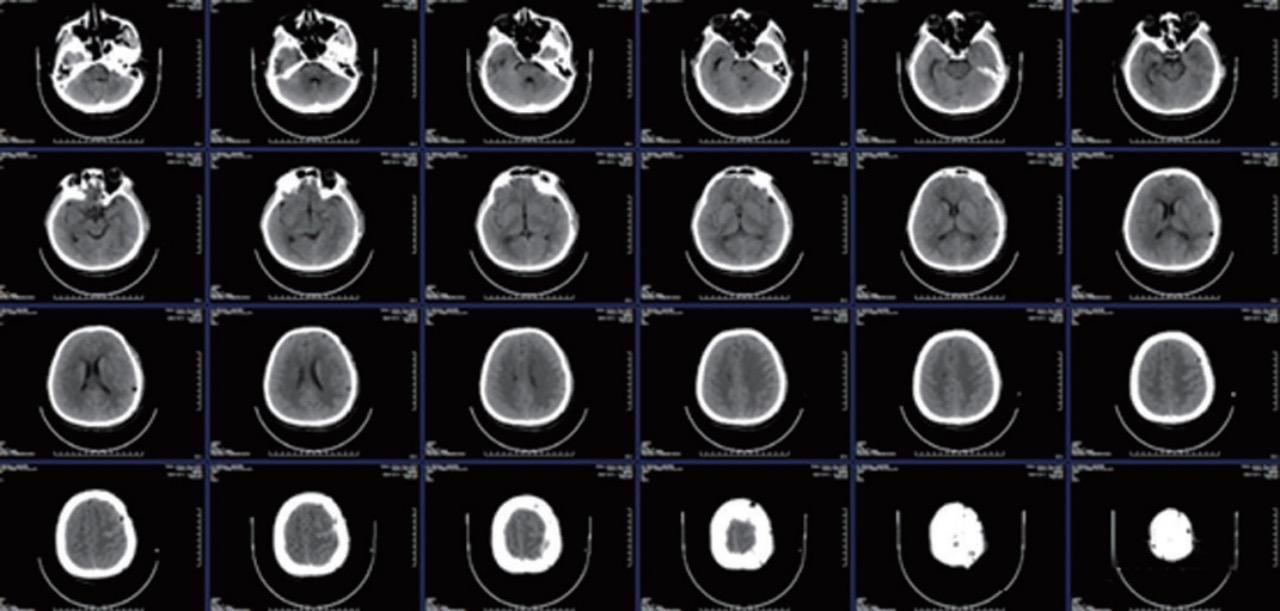

病例 |

患者左侧颅骨缺损导致外观严重受损,同时由于再次头部碰撞可能引起颅内损伤的风险显著增加。神经外科 医生为患者进行自体颅骨修补手术,成功重塑了完整的头颅结构。患者术后顺利返回病房,手术取得了安全 而有效的结果。

### Case of Autologous Bone Repair

A patient suffered from severe cosmetic deformity due to a defect in the left side of the skull, which also significantly increased the risk of intracranial injury from any subsequent head trauma. A neurosurgeon performed an autologous bone cranioplasty for the patient, successfully reconstructing the complete skull structure. The patient was safely and effectively returned to the ward post-surgery, with the operation yielding successful and effective results.